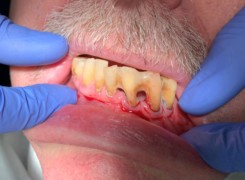

Pan Ryszard trafił do Naszego Gabinetu z jasno sprecyzowanym oczekiwaniem. Miał 84 lata i chciał odzyskać możliwość swobodnego spożywania posiłków oraz poprawienia sobie komfortu życia a także prosił aby przywrócić mu piękny uśmiech jakim cieszył się przed laty. Już na początku pierwszej rozmowy zastrzegł, że interesuje go wyłączenie rozwiązanie uzupełnieniem protetycznym stałym. Nie miał zamiaru użytkować żadnych protez ruchomych. Mając na uwadze powyższe wykonaliśmy Panu Ryszardowi zdjęcie pantomograficzne oraz badanie tomograficzne szczęki i żuchwy na postawie których zapanowywaliśmy Pacjentowi optymalne rozwiązanie – stałe uzupełnienie protetyczne w postaci 28 koron cyrkonowych zamontowanych do dwóch belek cyrkonowych które będą przymocowane do 16 implantów w konfiguracji 8 wszczepów w szczęcie 8 w żuchwie. Po omówieniu powyższego planu przystąpiliśmy do Wspólnej pracy której efekty w poszczególnych etapach prezentujemy poniżej.